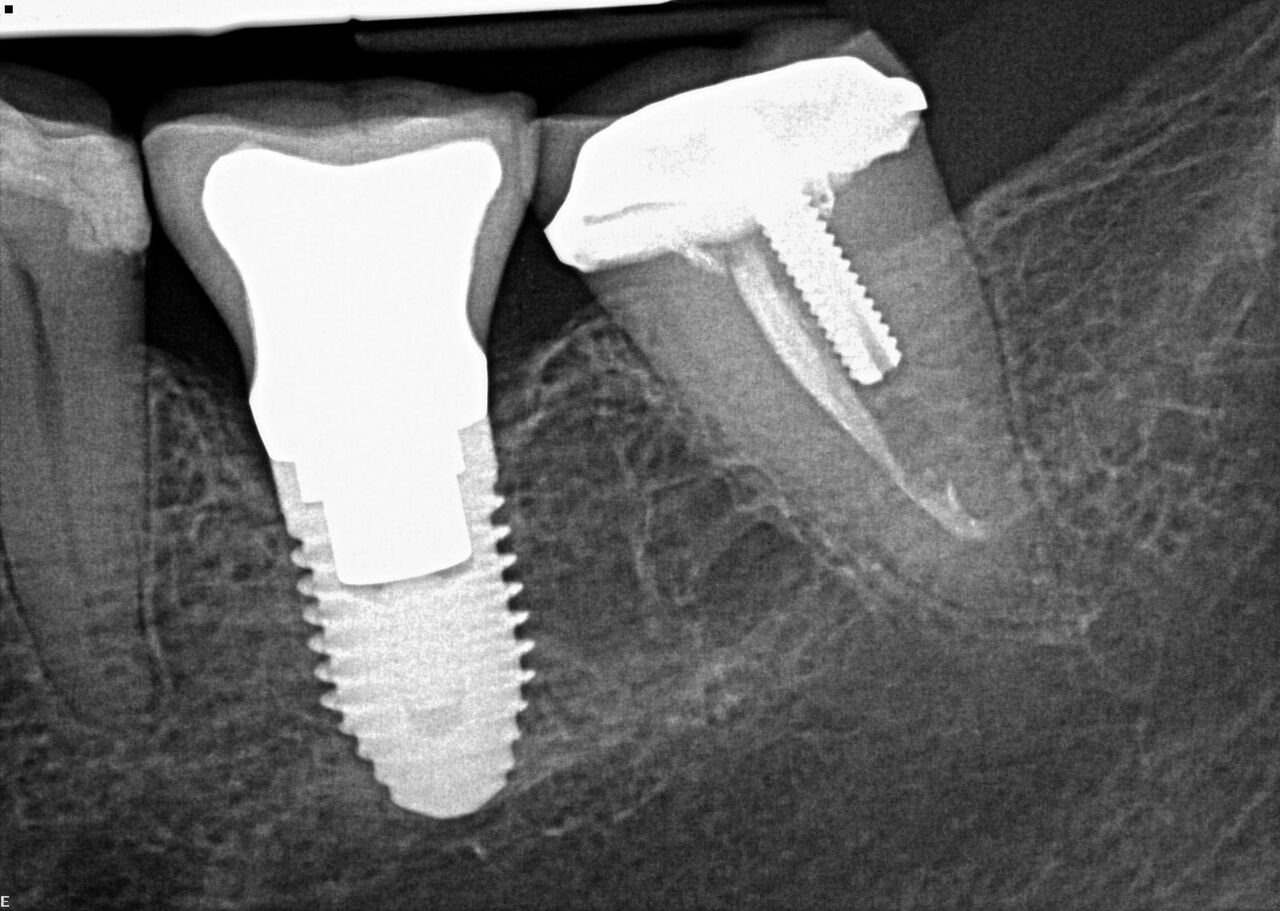

(4.) Radiograph showing immediate implant of No. 19 with immediate restoration day of surgery.

Figure 4

(6.) 1-year postoperative radiograph of No. 19 IIIPR.

Figure 6

A 63-year-old woman presented with severe pain on biting of tooth No. 19 (Figure 1). Clinically there was pain on percussion and significant periodontal probing along the mesial root. The patient was anesthetized with infiltration anesthesia and the crown was horizontally sectioned from the lingual of the tooth. The remaining tooth was sectioned so the roots could be extracted individually. The socket was fully debrided and an implant was placed (Figure 2), which was prosthetically correct and stabilized in excess of 45 Ncm. The bone was milled to allow for unimpeded placement of a temporization abutment. The initial crown was revised to be the temporary crown in infraocclusion. Cement was extruded extraorally (Figure 3) prior to seating of the temporary restoration. The socket was sealed with the temporary crown and there were no sutures or bone graft (Figure 4 and Figure 5).

The patient was instructed in postoperative care specific to an immediately provisionally restored implant and an antibiotic and analgesic was prescribed. At 4 months, integration was confirmed. The patient was impressed for a final restoration that was cemented within 2 weeks. The final radiograph (Figure 6) and clinical photo (Figure 7) presents a 1-year postoperative demonstrating good esthetics, full bone regeneration, and a steady state of bone to the implant under loading.